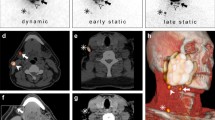

Imaging report

A nuclear medicine report has to include several factors such as: (a) visualisation of lymphatic ducts, (b) order of appearance, (c) lymph node basin and (d) intensity of lymph node uptake [37]. On the basis of these factors, visualised radioactive lymph nodes may be considered definite SLNs (when lymph nodes draining from the site of the primary tumour are visualised with their own afferent lymphatic vessel or when a single radioactive lymph node in a lymph node basin is seen) [38], highly probable SLNs (when lymph nodes appear between the injection site and a first draining node or when nodes with increasing uptake appear in other lymph node stations), or less probable SLNs (second-echelon lymph nodes in the head and neck). These aspects are highlighted in Figs. 1 and 2.

Lymphatic drainage to the neck is unilateral in a 55-year-old male patient with a T1 primary tumour localized on the right side of the tongue (on the left) and bilateral in a 72-year old female patient with a T1 midline tongue carcinoma (on the right). Note that in both cases the sternocleidomastoid muscle, as depicted on volume rendering and cross-sectional SPECT/CT, is an excellent landmark to anatomically refer the location of sentinel lymph nodes in relation to lymphatic basin and surgical neck level

Schematic imaging report generation with a summary of interpretation criteria for lymphoscintigraphy (on the left) and SPECT/CT (on the right) for a 61-year-old male patient with a T2 midline floor of mouth carcinoma. On dynamic images there is only visualization of activity along throat and oesophagus but no evident lymph node uptake. By contrast, on early static images initial lymph node uptake on the right side of the neck is seen with increasing intensity on delayed static images, which also show drainage to the left side. On SPECT/CT sentinel lymph nodes in level II and III of both sides of the neck are seen whereas the radioactivity just behind the injection site on the right is associated with internal contamination along the oropharynx

In general, early planar imaging helps to identify the order of drainage. First, draining lymph nodes as SLNs by visualisation of lymphatic ducts (Fig. 1). These lymph nodes can be distinguished from second-echelon lymph nodes, which mostly appear on delayed planar images. In other cases, a single lymph node is seen on early and/or delayed images. This lymph node is also considered a definite SLN. Due to its increased sensitivity, SPECT/CT may detect additional lymph nodes in other basins such as the contralateral side of the neck. It should be emphasised, particularly in the contralateral neck even if the signal is relatively weak, that these lymph nodes might be considered highly probable SLNs. Less frequently, a radioactive lymph node may appear later and more proximal to the oral cavity injection site than a first draining node; its increasing uptake on delayed images can confirm this lymph node as a highly probable SLN and help to distinguish it from prolonged activity at a lymphatic duct valve, which usually shows decreasing intensity on delayed images [39]. In specific cases, contrast enhanced (ce) SPECT/CT, or image fusion with ceCT or ceMR, may provide an additional value, at the expense of increased complexity of the procedure. Recently, a new MRI technology called D-Prep MRI was introduced based on its ability to more clearly delineate LNs [40].

For reading/reporting purposes, SPECT/CT images are mostly displayed in a manner similar to that of conventional tomography. The two-dimensional display of fused images to be correlated with CT and SPECT is facilitated by multiplanar 3D reconstruction, and the use of cross-reference lines allows navigation between axial, coronal, and sagittal views. At the same time, this tool enables the correlation of radioactive SLNs seen on fused SPECT/CT with lymph nodes seen on CT. Most frequently, a radioactive SLN corresponds to a single lymph node on CT, but in some cases it correlates with a cluster of lymph nodes. This information may be useful for the intraoperative procedure and the post-excision control using portable gamma cameras or probes, as more radioactive SLNs may be harvested at the same location.

The use of maximum intensity projection (MIP) to display fused SPECT/CT images may also help surgeons to anatomically recognise and localise SLNs. MIP is a specific type of rendering in which the brightest voxels are projected into a three-dimensional image. A limitation of MIP is that the presence of other high-attenuation voxels on CT may make it difficult to recognise the vasculature and other anatomical structures. Further, MIP provides a two-dimensional representation, which cannot accurately depict the actual relationships of the vessels and other structures. SLN localization in a three-dimensional context can also be supported by the application of volume rendering (VR). In this modality, different colours are assigned to anatomical structures such as vessels, muscles, bones, and skin. This results in easily recognisable anatomical reference points facilitating the localisation of SLNs, for instance, in relation to the vasculature. By incorporating a colour display, VR improves visualisation of complex anatomy and 3D relationships, facilitating correlation with cross-sectional analysis. Interpretation of the VR images is more intuitive than that of axial cross sections and helps identify the anatomical context of the SLNs. It is also very helpful to the surgeon if the nuclear medicine report indicates the position of the SN in relation to local anatomical structure. This is normally local muscles such as the bellies of digastric or omohyoid, and in particular the jugular vein. The lymphatic drainage from oral cancer is invariably to nodes along the jugular vein. SNs posterior to the jugular vein and omohyoid muscle can be difficult to find through a limited access incision, and it is particularly helpful to be aware of their presence prior to surgery.

Identification and localization of SLNs in the nuclear medicine report need to be related to the anatomical and surgical approach. According to the American Joint Committee on Cancer (AJCC)–Union for International Cancer Control (UICC) TNM (tumour, node, metastases) staging system, the lymph nodes in the neck may be subdivided into specific anatomic subsites and grouped into seven levels in each side of the neck (Fig. 2). Level I includes the submental (sublevel Ia) and submandibular (sublevel Ib) lymph nodes. Level II contains the upper jugular lymph nodes that extend from the inferior border of the hyoid bone to the base of the skull; in relation to the vertical plane delineated by the spinal accessory nerve, the lymph nodes located anteriorly (medial) constitute sublevel IIa, and the nodes located posteriorly (lateral) correspond to sublevel IIb. Level III includes the middle jugular nodes (cranial to the cricoid), and level IV the lower jugular nodes (caudal to the cricoid). The posterior border of regions II, III, and IV is the posterior border of the sternocleidomastoid muscle, which is the anterior border of level V. This latter group is composed of the sublevels Va (which includes the spinal accessory nodes) and Vb (which includes lymph nodes along the transverse cervical vessels) and the supraclavicular lymph nodes (with the exception of the Virchow node, which is located in level IV). Level VI contains the pretracheal and paratracheal nodes, the precricoid Delphian node, and the perithyroidal nodes, including the lymph nodes along the recurrent laryngeal nerves. Finally, level VII includes the superior mediastinal lymph nodes [41, 42].

Summarizing, each component of the lymphatic mapping procedure needs to be described incorporating the above-mentioned criteria (Fig. 2).